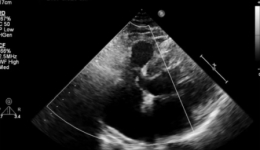

近日,宋先生(化姓)因心脏不适来我院进行超声心动图检查时,医生发现其室间隔上部存在连续性中断,三尖瓣隔瓣与室间隔缺损的右室面黏连,并在瓣尖部观察到5mm的缺损,缺损上缘距离主动脉右冠瓣仅2mm。未发现主动脉瓣脱垂和反流(见图一)。于是,...